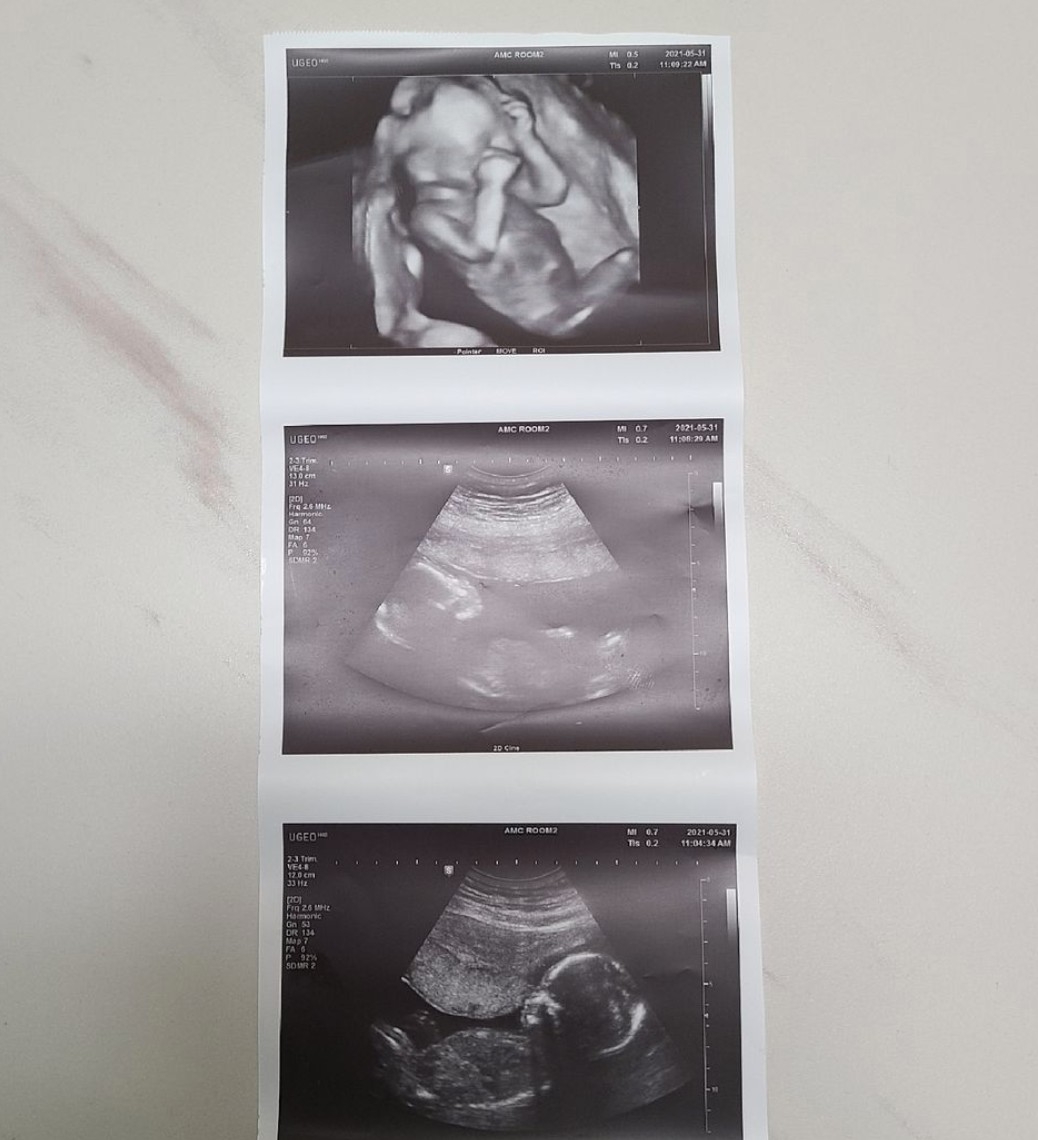

黃信英在懷孕前的體重是71公斤,雖然目前還未生產,但她在懷孕的過程中,都會記錄自己慢慢增加的體重與寶寶在肚子內長大的體態,想要留下這份特殊的懷孕過程記錄,給將來長大的孩子們看。